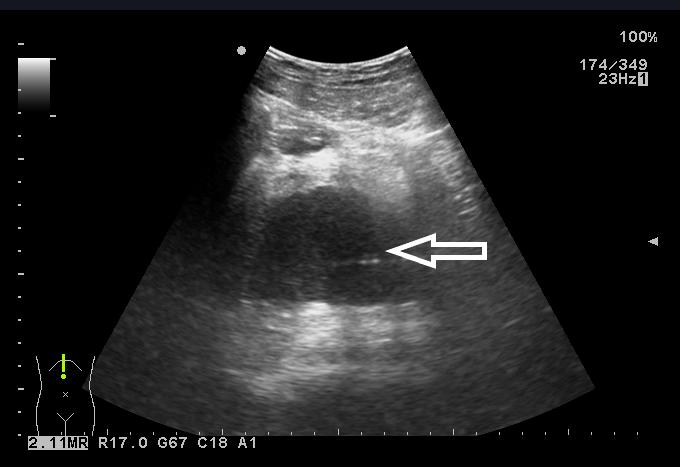

患者入院后完善相关检查,血常规:白细胞6.73×109/L,中性粒细胞4.87×109/L,血小板126×109/L;C-反应蛋白 > 90 mg/L;降钙素原7.6 ng/mL;凝血功能:PT 15 s。盆腔超声显示:骶前间隙可见一80 mm×46 mm的无回声区,内可见斑点样中强回声(图 2)。排除禁忌后,于入院当晚行超声引导下穿刺置管引流术,由于脓肿位置较深,经腹途径有肠管﹑膀胱和直肠的遮挡,所以本中心决定选择超声引导下经臀穿刺引流术。

|

| 图 2 盆腔超声显示:骶前间隙可见一80 mm×46 mm的无回声区,内可见斑点样中强回声 |